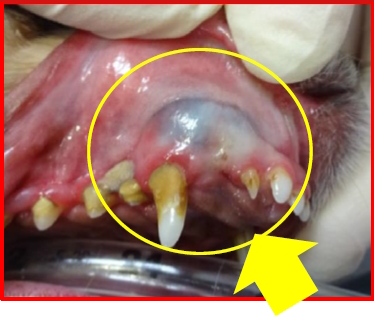

上の写真の黄色矢印の部分が腫れています。口の中を確認したところ、下の写真のように、犬歯の上の部分がプヨプヨした状態で腫れていました。この場所を全身麻酔下にて検査をしたところ、下記のような状態であることがわかりました。

ブヨブヨしていた原因は「嚢胞」と呼ばれる液体がたまったものであり、この子の場合は「埋伏歯」が原因で嚢胞が発生していましたので、「歯原性嚢胞」と診断しました。埋伏歯とは、文字通り歯肉の下に埋まっている歯のことで、正常に歯が生えなかった歯のことを言います。この埋伏歯があるかどうかは見た目だけでは分からず、歯科レントゲンや CT 検査などの画像診断を実施しないと診断ができません。また、埋伏歯が存在することで、上記のような歯原性嚢胞を形成することがあり、放っておくと顎の骨を溶かすように大きくなってきます。この子も嚢胞 のせいで顎の骨が溶かされていました。溶けている部分の顎の骨は完全に再生しませんが、これ以上悪化させないために外科手術にて嚢胞の切除と、抜歯処置を実施しました。現在、嚢胞が再発しないか経過を見させていただいております。